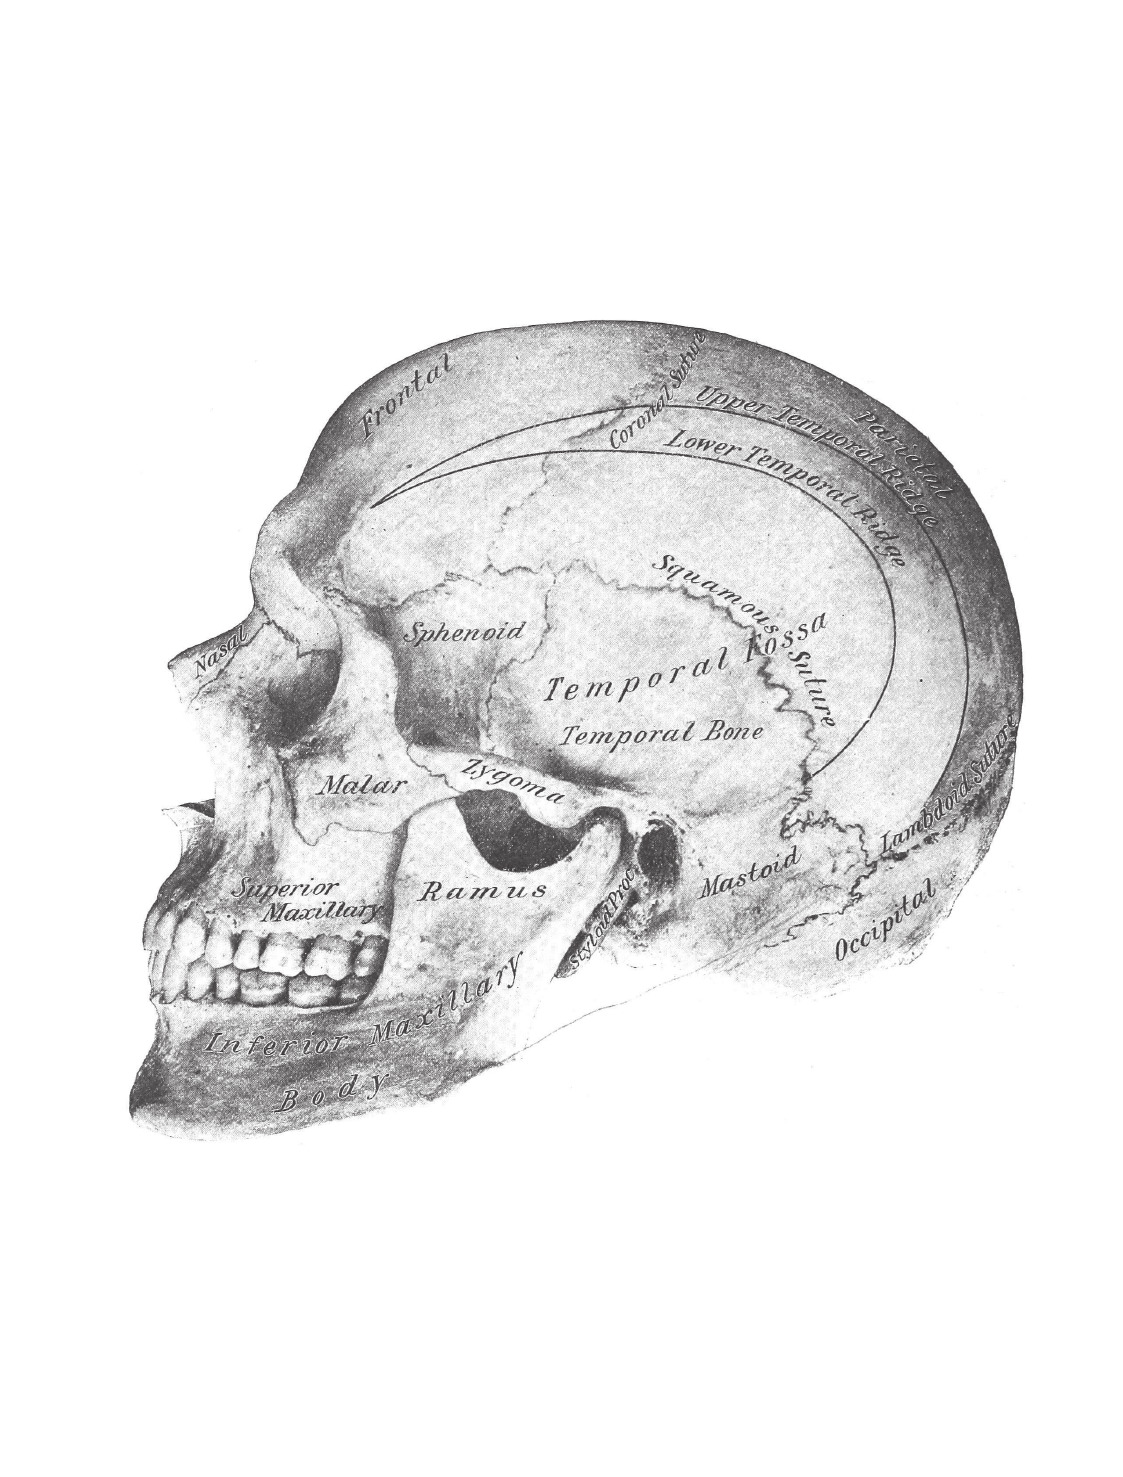

Написанная в 1850-х годах молодым врачом Генри Греем, "Анатомия Грея" была самой всеобъемлющей и доступной анатомией своего времени. Книга, которую вы держите в руках, содержит исторический текст второго издания и все авторские рисунки Генри Вандайка Карт

Написанная в 1850-х годах молодым врачом Генри Греем, "Анатомия Грея" была самой всеобъемлющей и доступной анатомией своего времени. Книга, которую вы держите в руках, содержит исторический текст второго издания и все авторские рисунки Генри Вандайка Карт